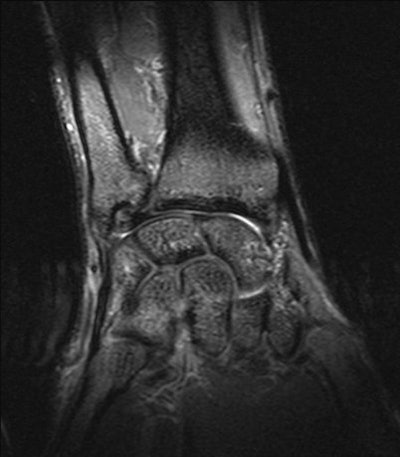

Hamate Fracture

History: A 20-year-old male outfielder who hits left-handed swung and missed the ball. He experienced immediate hypothenar eminence pain. Clinical examination showed tenderness over the muscle belly of the hypothenar eminence in the palm of the hand. No wrist pain or tenderness; demonstrated full range of motion in wrist and fingers. Grip strength was near normal the day after the injury. X-rays, including carpal-tunnel view, were inconclusive for pathology. MRI made the diagnosis of a fracture of the hook of the hamate. Significance: This injury almost always occurs in a hitter who swings and misses and has immediate ulnar palm pain. It is always the bottom hand with which the player holds the bat. This is the significance of this player being a left-handed batter. The bottom hand in the batting position is the right hand in a left-handed batter. The precise mechanism of injury is unclear, but theory has it that the hook of the hamate bangs mechanically against the knob of the bat. Treatment: The San Francisco Giants have found that most if not all such fractures deteriorate to non-union, becoming chronically symptomatic. Therefore, excision of the fractured hook is performed as soon as the diagnosis is made. Return to full competition is usually possible within 6 weeks, although players have returned as early as 3-4 weeks. Image and case study courtesy of the San Francisco Giants and Clinical Diagnostic Radiology, Phoenix. |